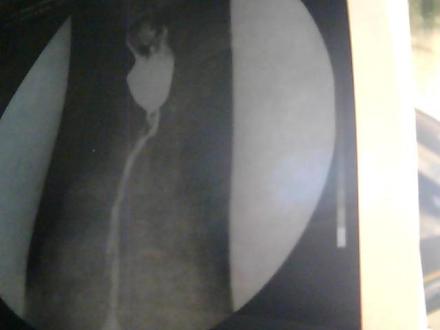

食道癌诊断方法之X线钡餐造影:该方法除极早期食管癌不易显示外,有经验的放射科医师充分调好钡剂,令病人分次小口吞咽,多方位仔细观察和气钡双重造影,大多能发现食管黏膜增粗、迂曲或虚线状中断;或食管边缘发毛;或小的充盈缺损;或小的龛影;或局限性管壁发僵;或有钡滞留等较早癌的征像。

(1)食管钡餐检查:检查可观察食管的蠕动状况、管壁的舒张度、食管黏膜改变、食管充盈缺损和梗阻程度。食管蠕动停顿或逆蠕动,食管壁局部僵硬不能充分扩张,食管黏膜紊乱、中断和破坏,食管管腔狭窄,不规则充盈缺损、溃疡或瘘管形成及食管轴向异常等均为食管癌的重要征象。低张双重造影对早期食管癌的检出较常规造影更有效。